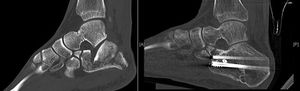

Postoperative CT (defined as that performed prior to hospital discharge of the patient or in the first month of follow-up) was performed only in those cases in which the surgeon considered that pain radiology would not clarify the quality of the joint reduction, resulting in a total of 17 cases (37% of the series, six Sanders type IV patients treated with the “L” approach, nine Sanders type III patients treated by sinus tarsi and two Sanders type II patients treated with closed reduction and fixation with screws). The reduction of the posterior subtalar joint measured by CT was satisfactory in 12 cases (defined as an articular displacement < 2 mm). In the other five cases the displacement was above 2 mm (one Sanders type iv case, one Sanders type iii case of tarsi sinus, one Sanders type iii case with indirect reduction and cannulated screws and two Sanders type ii cases also with indirect reduction). Reintervention was decided in only one case (patient with Sanders type II fracture) with an “L” approach and low-profile plate, with good radiological and functional outcome. Of the remaining four cases the risk/benefit balance of further surgery called for conservative treatment, particularly due to the further aggression to soft tissues. The average preoperative Böhler angle was 6.45 ± 10.21 ([-22]-25) and postoperative angle was 20.46 ± 7.09 (4−38). CT in follow-up (defined as over one year after surgery) was performed in 31 cases, only in those where three was suspicion of a post-traumatic degenerative pathology following analysis of plain radiology: subtalar osteoarthritis was diagnosed in 19 cases (symptomatic in 12, seven of them treated with subtalar arthrodesis) and calcaneo-cuboid osteoarthritis in six cases (only one symptomatic and treated conservatively) (Table 3). The AOFAS was 74.28 ± 18.98 (27−100) and the VAS 4.14 ± 2.98 (2–9).

A CT revealing an articular displacement under 2 mm was statistically significant in 12 patients of our series with better outcome in the AOFAS scale (77.17 points on average) and lower than average VAS (2.83), p = .002. Regarding the Böhler angle, the relationship of an angle > 20° with higher AOFAS (80.82) and lower VAS (3.18), p = .001 was significant (Table 4).